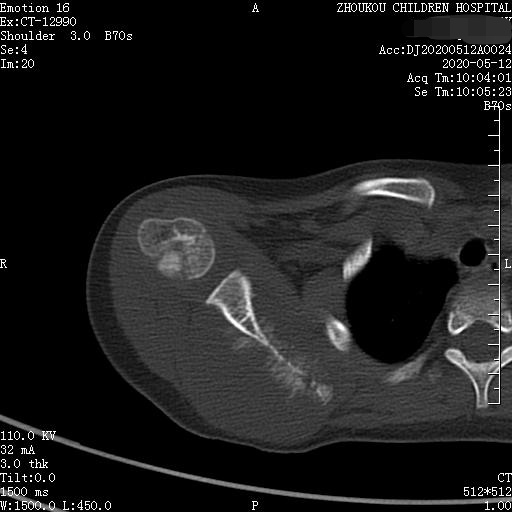

通过CT平扫发现:右侧肩胛骨骨质密度不均,骨质内可见“虫食样”低密度影,骨质边缘可见多发放射状骨针,呈“日光射线征”。周围软组织明显肿胀,肌间隙模糊。CT检查意见:考虑:右肩胛骨占位,骨肉瘤可能,不除外其它恶性肿瘤病变,请结合临床及相关检查注意复查。 影像鉴别诊断:骨肉瘤是指起源于骨间叶组织,遗留形成骨细胞直接形成骨样组织为特征的恶性肿瘤,是比较常见的骨恶性肿瘤,好发于十到二十岁青少年,骨肉瘤常见于管状骨,股骨远端胫骨近端最多见,表现为疼痛局部肿胀运动障碍,实验室检查都有碱性磷酸酶升高。

转移性骨肿瘤是最常见的恶性骨肿瘤,约占恶性骨肿瘤的75%。CT表现一般为溶骨型、成骨型、混合型。同一肿瘤的转移可表现为溶骨与成骨转移两种类型,同一病灶上可出现溶骨与成骨两种表现,少数转移灶呈囊状膨胀性破坏。脊柱的溶骨性转移累及附件并形成椎旁软组织肿块。前列腺癌、结肠癌、类癌的成骨性肋骨转移可表现为膨胀性硬化。前列腺癌容易转移到骨盆,鼻咽癌容易转移到脊柱。肾癌骨转移常为单发、溶骨性且呈多囊状或泡沫状,可伴有骨性房隔、局部膨胀性改变。颅骨溶骨性转移灶有时在溶骨区中央可见残留的正常骨或者密度增高骨,即常说的靶性病变。 术后随访家属得知:病人术后临床医生怀疑骨转移瘤(孩子过去有视网膜母细胞瘤一侧眼球摘除史)或神经外胚层性肿瘤?,建议基因方面检测。